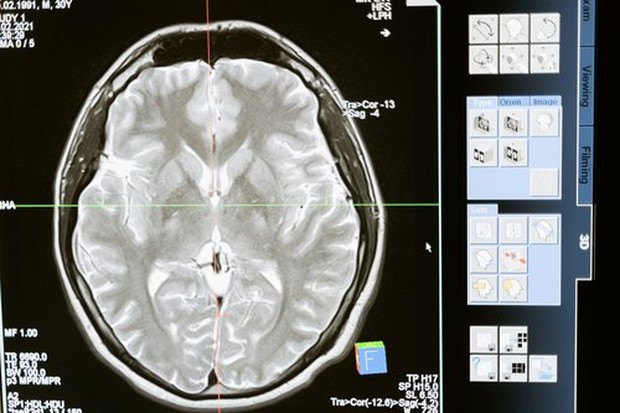

Beauties, koma adalah kondisi seseorang, yang sudah dianggap darurat oleh medis, karena mengalami ketidaksadaran dalam waktu yang lama, akibat adanya penurunan aktivitas otak. Lalu apa sih, yang terjadi, pada tubuh seorang pasien yang koma? Yuk cari tahu penjelasannya!

Koma disebabkan adanya pembengkakan yang terjadi pada jaringan otak. Pembengkakan tersebut dapat membuat otak terjepit dan mengalami tekanan, sehingga oksigen dalam otak nggak bisa terdistribusi dengan baik. Nah, hal ini bisa membuat aktivitas otak menjadi terganggu, Beauties.

Aktivitas otak yang terganggu, membuat otak nggak mampu mengeluarkan zat-zat dan cairan beracun yang ada pada tubuh. Pada akhirnya, cairan yang nggak bisa dikeluarkan, akan menggenang di dalam otak, dan membuat seseorang mengalami koma.